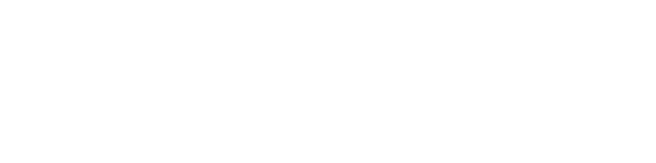

AI Cells 自體血液單核細胞純化流程、中後期退化性關節炎治療

AI Cells 自體血液單核細胞純化流程主要分為五個步驟:第一步為採集血液 50–80 ml;第二步為前置紅血球分離;第三步為進行血液細胞純化作業,約 150 分鐘,並採用純化細胞專用的高階封閉式純化設備系統(通過衛福部二類醫材許可),可降低外來污染風險並提高安全性;第四步為抽取血液細胞純化液,約 4–5 ml;第五步則由專科醫師為病人進行注射治療。

自體血液單核細胞純化流程

AI Cells 自體血液單核細胞純化流程主要分為五個步驟,從抽血、純化到施打,整體製備時間約 150 分鐘。

- 採集血液:抽取 50–80 ml 自體血液。

- 前置紅血球分離:先進行血液前處理,作為後續純化基礎。

- 進行血液細胞純化作業:約 150 分鐘,採用純化細胞專用的高階封閉式純化設備系統(通過衛福部二類醫材許可),可降低外來污染風險,安全性更高。

- 抽取血液細胞純化液:取得約 4–5 ml 純化液。

- 專科醫師施打:由專科醫師為病人進行注射治療。

PCP / AI Cells 純化流程與產品成分

PCP 周邊血液單核細胞純化技術的主要流程包含:抽血 50–80 c.c.、單核球富集、去除嗜中性球、細胞定量與品質管制,以及由專科醫師施打。產品成分圖中顯示,純化後的 AI Cells 主要組成以淋巴球與單核球為主,其中單核球約占 20%,可作為支持療程抗發炎與修復概念的重要基礎。